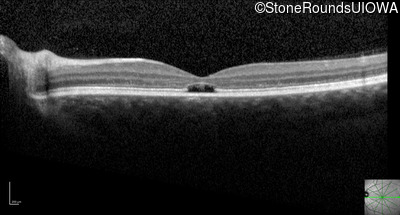

Optical Coherence Tomography - Left - 20/40

Exemplar / OCT Stack

OCT Stack